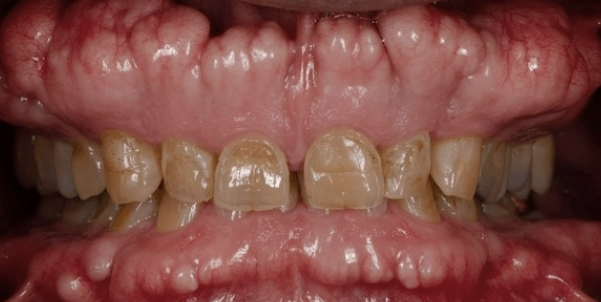

how would you describe this lesion?

generalized grey/ white lesion